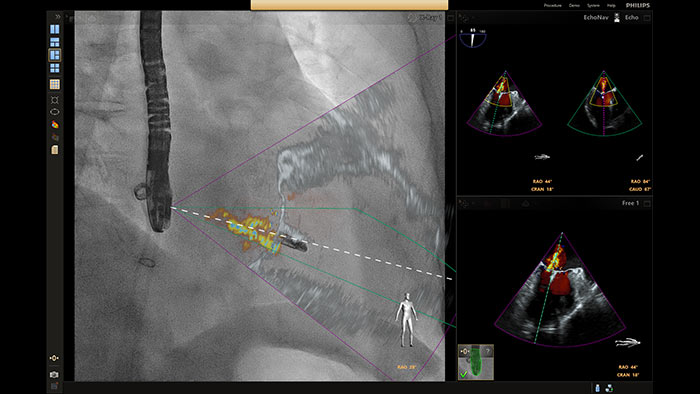

En el centro de nuestra suite, la exclusiva solución EchoNavigator es el ejemplo emblemático del compromiso de Philips con la multimodalidad y la integración del flujo de trabajo, aporta lo mejor de ambos mundos del líder de la industria en soluciones cardíacas intervencionistas de rayos X y ecografía.

Visualización de la reparación mitral de la regurgitación posimplante

Guía de punción transeptal mediante EchoNavigator